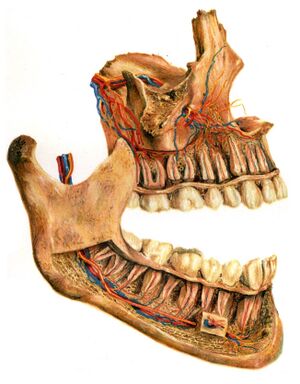

Structure

On the maxilla, the alveolar process is a ridge on the inferior surface, making up the thickest part of the bone. On the mandible it is a ridge on the superior surface. The structures hold the teeth and are encased by gums as part of the oral cavity.[11] The alveolar process comprises cells and periosteum, also encompassing nerves, blood vessels, and lymphatic vessels.The alveolar crest terminates uniformly at about the neck of the teeth (within about 1 to 2 millimetres in a healthy specimen), while the alveolar process terminates along the line of the mandibular canal.[12]

The alveolar process proper encases the tooth sockets, and contains a lining of compact bone around the roots of the teeth, called the lamina dura. This is attached by the periodontal ligament (PDL) to the root cementum. Although the alveolar process is composed of compact bone, it may be called the cribriform plate because it contains numerous openings known as Volkmann's canals, which allow blood vessels to pass between the alveolar bone and the PDL. The alveolar bone proper is also called bundle bone because Sharpey fibers, part of the PDL, are inserted there. Sharpey fibers in alveolar bone proper are inserted at a right angle (just as with the cemental surface); they are fewer in number, but thicker in diameter than those found in cementum.[13]

The supporting alveolar bone consists of both cortical (compact) bone and trabecular bone. The cortical bone consists of plates on the facial and lingual surfaces of the alveolar bone. These cortical plates are usually about 1.5 to 3 mm thick over posterior teeth, but the thickness is highly variable around anterior teeth. The trabecular bone consists of cancellous bone that is located between the alveolar bone proper and the cortical plates.[14]